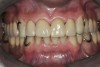

Figure 2  Intraoral occlusal view of maxillary dentition with the existing removable prosthesis presenting excessive signs of wear.

Figure 2

Initial examination revealed a partial edentulous patient with extensive wear of the maxillary anterior teeth and moderate wear in the mandibular teeth (Figure 1, Figure 2, Figure 3, Figure 4, Figure 5, Figure 6 and Figure 7). The patient’s maxillary and mandibular RPDs also showed excessive wear and multiple signs of fractures (Figure 2 and Figure 3). The patient had been wearing a mandibular nightguard for 8 years.